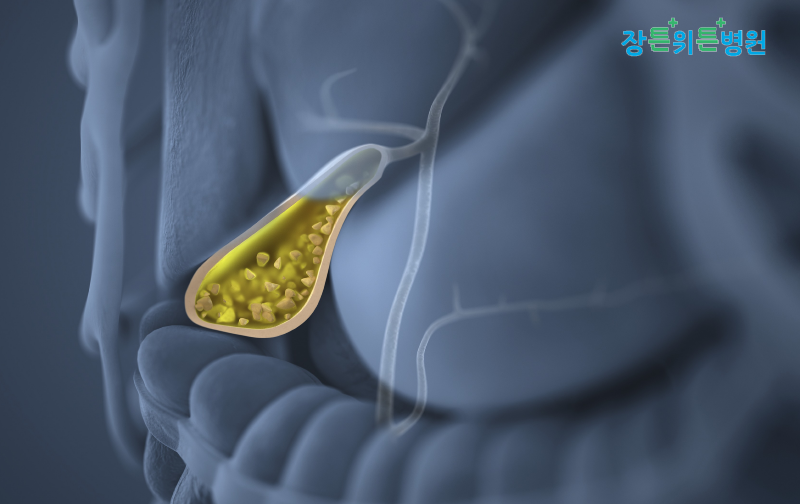

장관위튼병원 담석증의 증상 및 진단방법 1. 담석증이란?담석은 담낭에 생긴 돌을 뜻하는 것으로 담석에 의해 병이 발생한 상태를 담석증이라고 합니다.담낭에 석회만 있는 경우도 담석증에 해당하며, 담관에서 발생한 석회도 담석이라고 할 수 있습니다.담석이 있는 위치에 따라 담낭 내에 있으면 담낭 담석, 담관에 있으면 담관 담석으로 구분됩니다.

담즙은 간에서 하루 평균 700~8 00ml 정도 만들어지며 소화를 돕기 위해 만들어집니다.콜레스테롤과 지방, 담즙산, 빌리루빈 등이 포함이 되어 있는 것입니다.이 담즙이 담낭 안으로 비정상적으로 농축이 되면 담석이 형성되게 됩니다.담낭 안에서 만들어지는 담석은 대개 콜레스테롤 담석으로 담즙 내의 콜레스테롤과 포화상태에 따라 콜레스테롤 결정체가 만들어지며 이것이 굳어져서 발생합니다.